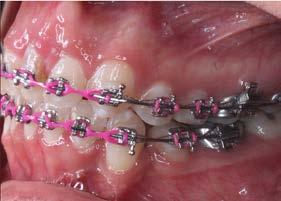

La paciente fue tratada con aparatología fija MBT slot 0.022”, se utilizaron bandas en primeros molares superiores e inferiores y tubos en segundos molares superiores, se realizaron extracciones de los dientes 11, 21, 34 y 44. Se colocaron los brackets de centrales en laterales, los de laterales en caninos y los de caninos en premolares.

En la fase de alineación se utilizó una secuencia de arcos comenzando con el arco 0.012” NiTi, 0.014” NiTi y 0.016” Niti. Se realizó la tracción del diente 21 y se mantuvo en boca hasta comenzar la fase de trabajo, posteriormente se realizó la extracción (Figura 3).

Durante la fase de trabajo se realizaron sets de intrusión y utilización de close coil; una vez cerrado el espacio entre los incisivos laterales, se indicó el uso de elásticos de clase III 3/16 4.5 oz para corregir la mordida borde a borde (Figura 4).